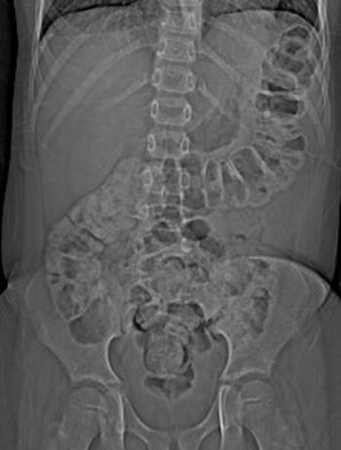

- radiografia abdominal:

alças do intestino delgado dilatadas, níveis hidroaéreos em todo o abdome

distensão gasosa do intestino grosso; volvo sugerido por alça intestinal em forma de feijão

alças do intestino dilatadas, pneumatose intestinal, gás na veia porta, ar livre, alça intestinal presa; ausência do padrão de gases normal no intestino